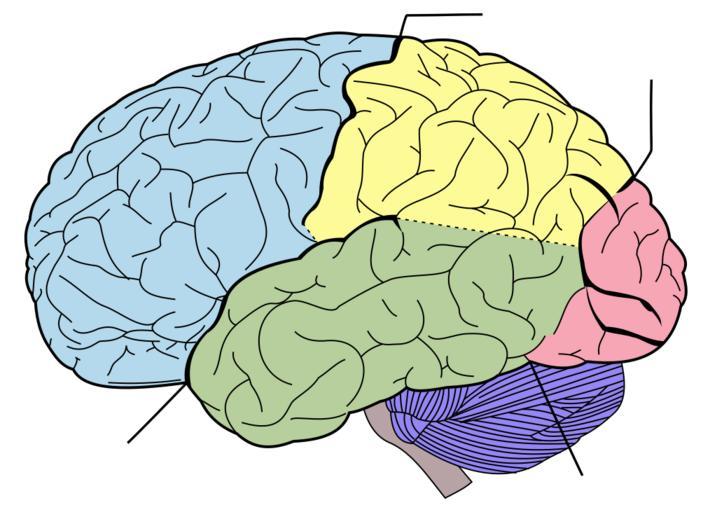

| Keywords: Brain diagram without text.svg en Principal fissures and lobes of the cerebrum viewed laterally Principal lobes of the cerebrum viewed laterally Figure 728 from Gray's Anatomy 4 lines note sulci as follows top center Central sulcus top right Parieto-occipital sulcus down left Lateral sulcus down right Preoccipital notch Õü┤ķ óŃüŗŃéēĶ”ŗŃü¤ŃāÆŃāłŃü«Ķä│Ńü«µ¦ŗķ Ā’╝łŃ ÄŃé░Ńā¼ŃéżŃü«Ķ¦ŻÕē¢ÕŁ”Ń ÅŃüŗŃéēÕ╝Ģńö©’╝ē Vectorized in CorelDraw by Mysid based on the online edition of Gray's Anatomy 2008-08-28 Mysid arrows were added by Was a bee Public domain <gallery> Image Gray728 svg English Version Image Brain diagram fr png French Version Image Brain diagram ja svg Japanese text Version Image Brain diagram pl svg Polish Version </gallery> Gray's Anatomy plate SVG files on human brain lateral view Brain lobes Lateral sulcus Central sulcus | ||||